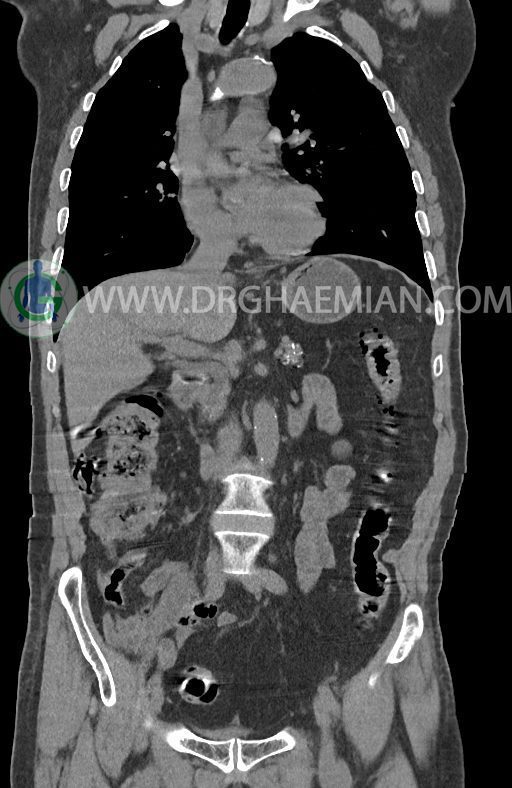

در سی تی اسکن اسپیرال ریه ها و مدیاستن، شکم و لگن با و بدون کنتراست وریدی (مولتی دیدکتور 16 با مقاطع ظریف و بازسازی کرونال) :

–توده هیپودنس به قطر 10mm در پارانشیم طحال مشهود است. Quadriphasic MRI پیشنهاد می گردد.

–آتروفی نسبی پانکراس همراه با فوکوس های کلسیفیه ی منتشر پارانشیم مطرح کننده ی پانکراتیت مزمن

-CBD بسیار دیلاته (16mm) همراه با دیلاتاسیون مجاری داخل کبدی سنترال بدون شواهد سنگ یا توده در مسیر

–کیست های کورتیکال متعدد هر دو کلیه به بزرگترین قطر 56mm

نتیجه : T(2or3)/N2/M0